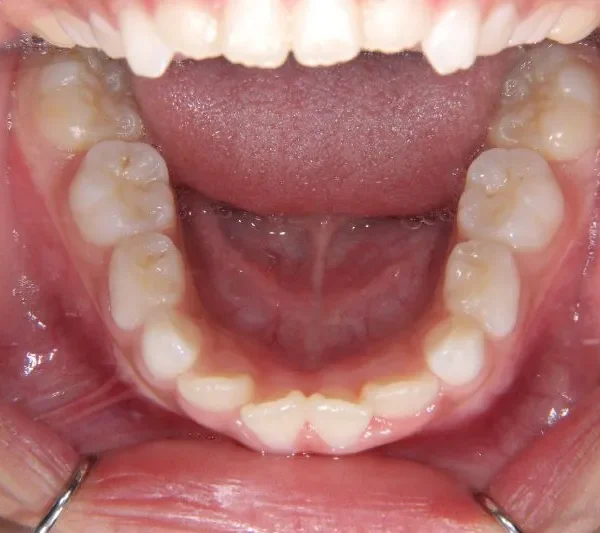

開咬・出っ歯・6歳女児【Y.A様】

状態 前歯で噛めない(開咬/オープンバイト)

前歯がかみ合っていません。

前歯は物を噛みちぎる(ハサミのような)役割をするのですが、歯と歯が離れていて本来の役割を果たしていません。

硬いものが嫌いな方や、噛むことが苦手な方に見受けられます。このまま、噛まずにいると

将来歯が残りにくくなります。